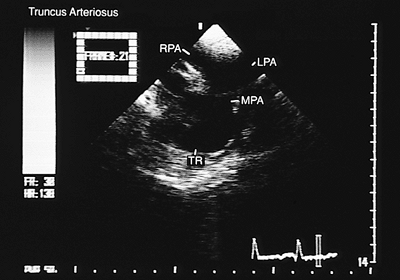

FIGURE 8.2.59. Truncus arteriosus. The origin of the main pulmonary artery (MPA) and its branches, the right pulmonary artery and the left pulmonary artery (RPA, LPA), from the posterior portion of the common truncus arteriosus (TR) can be identified in images in the transverse plane.

FIGURE 8.2.60. Pulmonary atresia. Longitudinal plane view. Overriding of the aortic valve (AV) over the ventricular septum (VS) can be seen. AO, aorta; LA, left atrium; LV, left ventricle; RV, right ventricle.

As the transducer is withdrawn to a plane slightly superior to the truncal valve, an attempt should be made to identify the emergence of the pulmonary artery or its branches from the posterior or lateral walls of the truncus arteriosus (Figs. 8.2.58 and 8.2.59).

When only one artery emerges from the heart, the V–A connection is defined as a single outlet. Three possibilities exist: truncus arteriosus, pulmonary atresia or aortic atresia. In truncus arteriosus, the vessel emerging from the heart originates the systemic, pulmonary, and coronary circulation. Images in the longitudinal plane obtained with a biplanar or multiplanar transducer show the truncus arteriosus straddling the interventricular septum (Fig. 8.2.57). The absence of right ventricular infundibulum is evident in transverse and longitudinal sections, and multiple images in both planes show the ventricular septal defect due to the absence of the infundibular septum. Transverse sections also show supernumerary truncal leaflets.